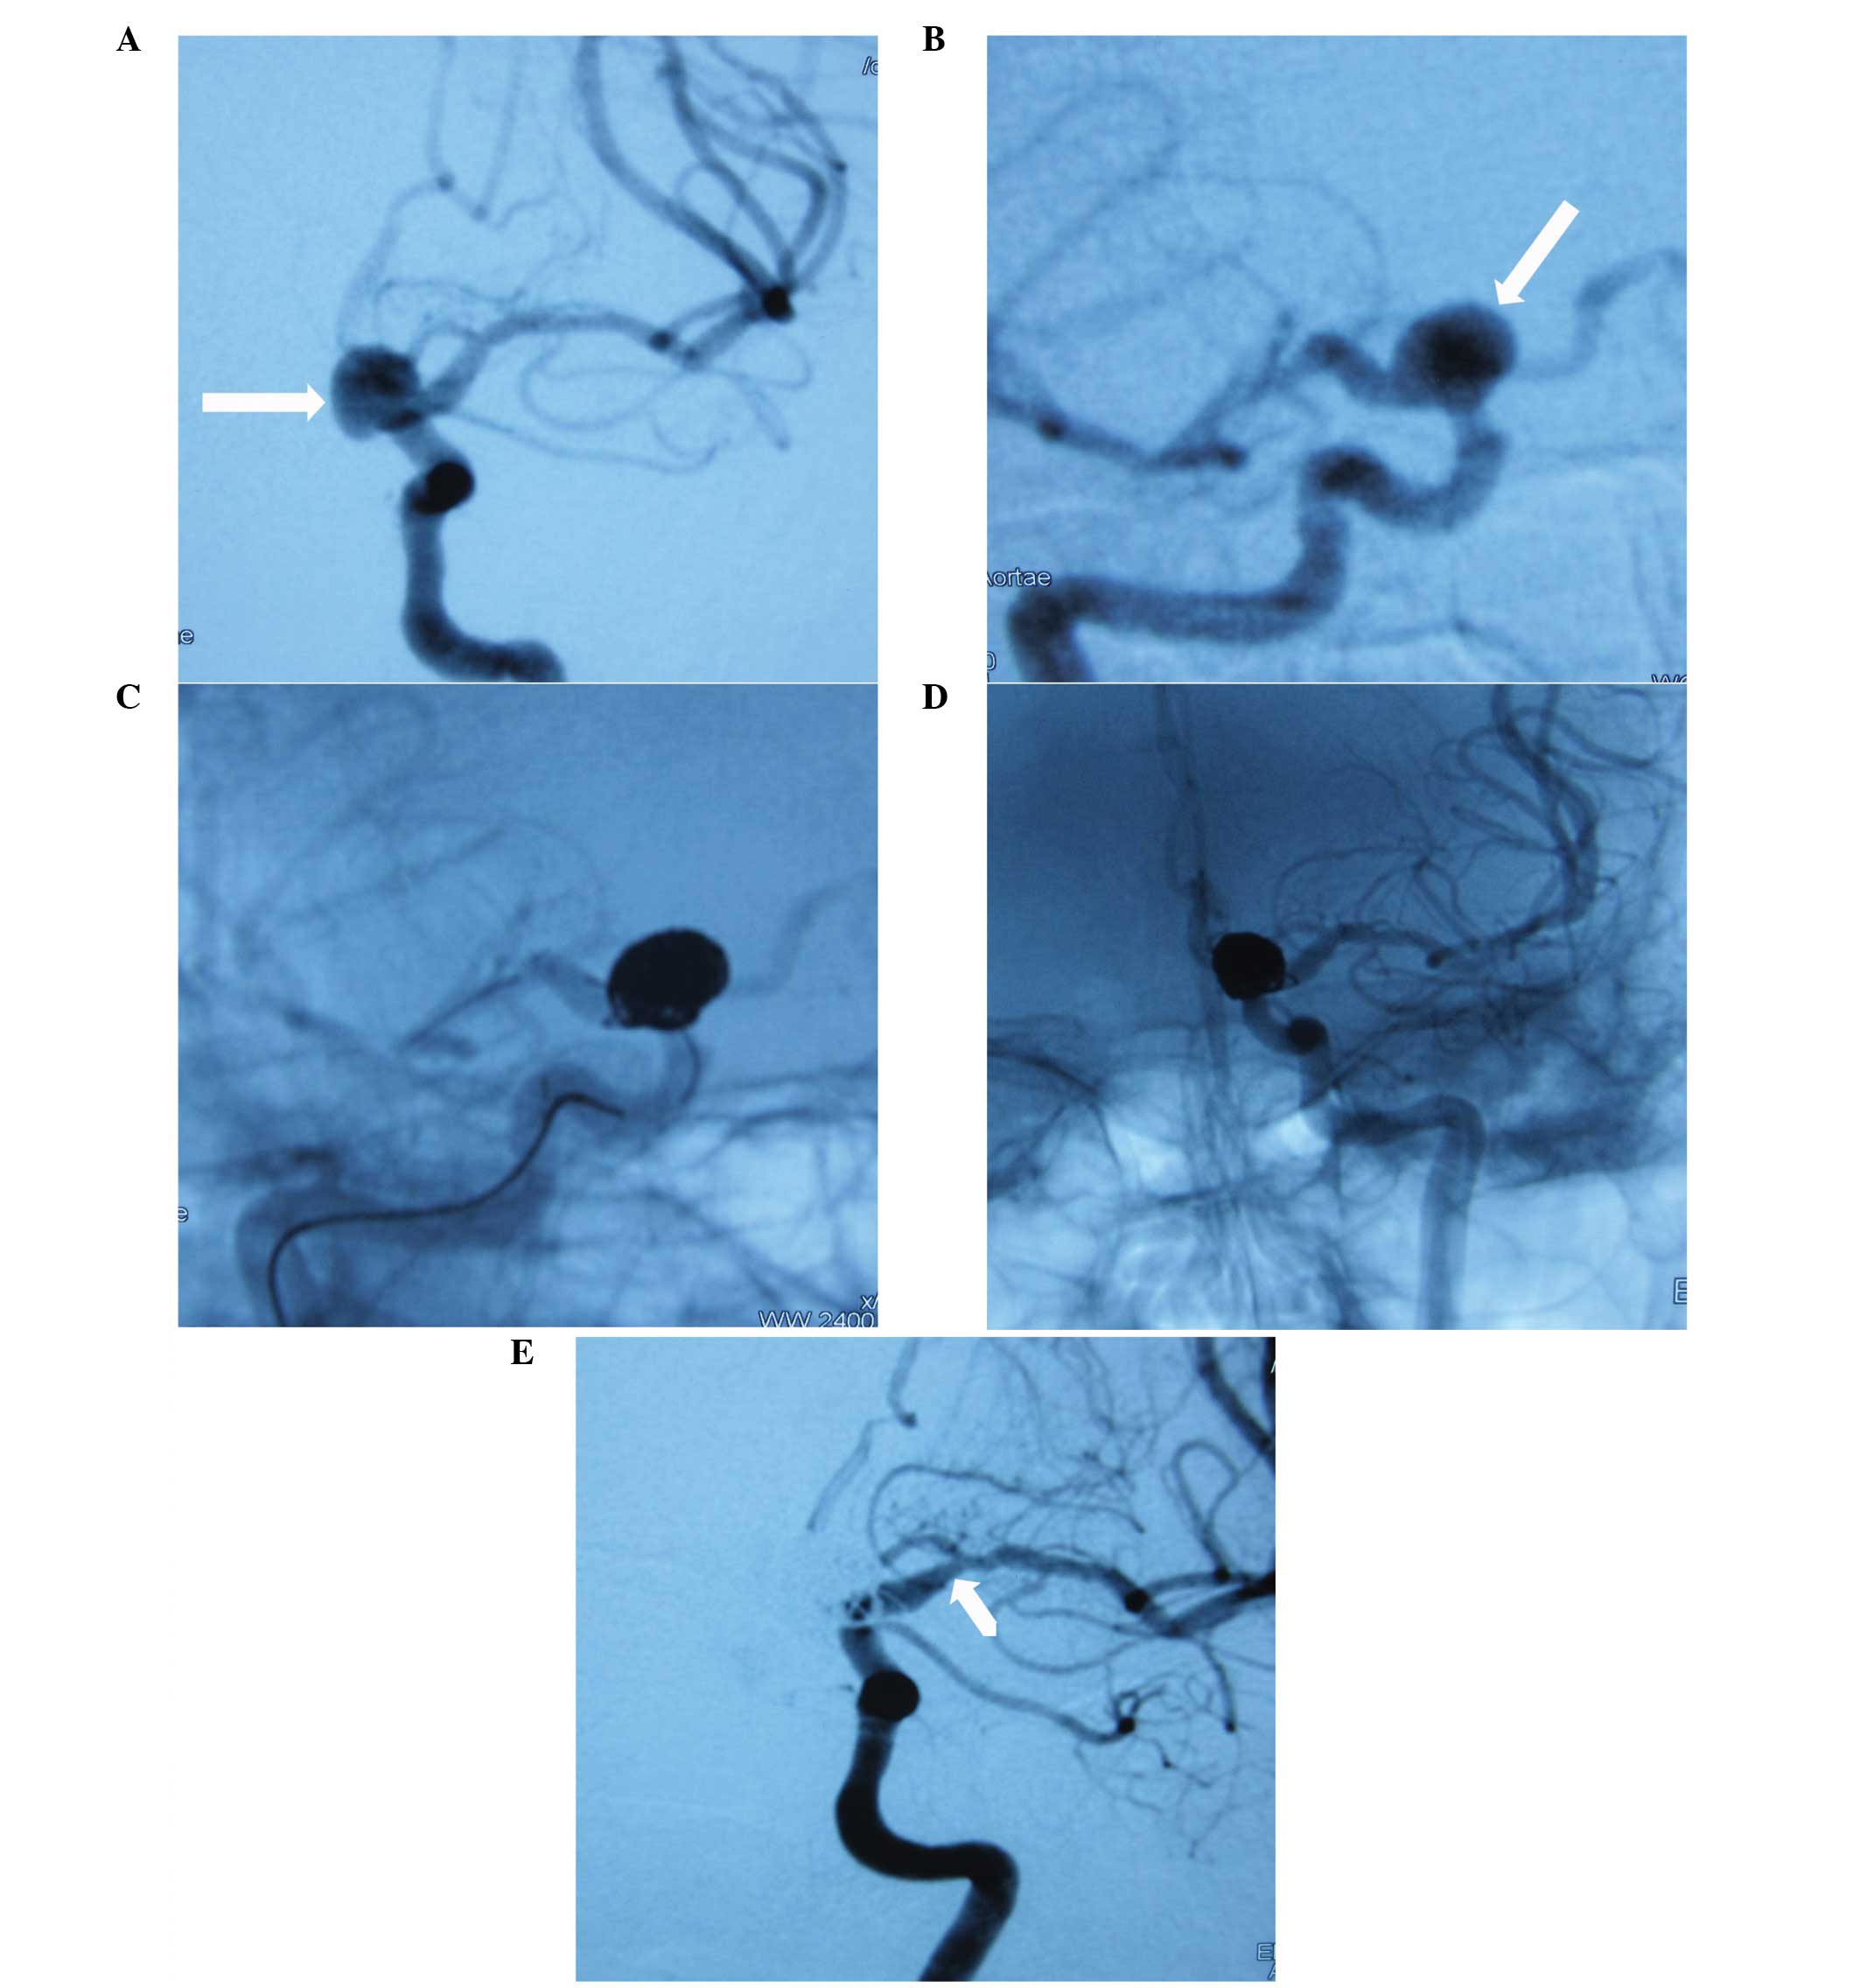

At the most recent angiographic follow-up post-embolization, 29/39 (74.4%) of the EP group and 36/51 (70.6%) patients in the ST group underwent cerebral angiography. The mean follow-up times in the EP and ST groups were 15.9±11.4 and 14.0±6.8 months, respectively. Changes in the angiographic outcomes in the EP group were as follows: Stable in 16/29 patients (55.2%), progressive occlusion in 11/29 patients (37.9%) and recurrence in 2/29 patients (6.9%). Changes in the angiographic outcomes in the ST group were as follows: Stable in 21/36 patients (58.3%), progressive occlusion in 13/36 patients (36.1%) and recurrence in 2/36 patients (5.6%). In total, 24/65 (36.9%) aneurysms that were followed-up underwent progressive occlusion (Table VI). In the four cases that demonstrated an aneurysm sac, recanalization was observed without further treatment since the recanalization was minor. Each group had one patient that presented with an in-stent stenosis at the follow-up (EP, Fig. 2; ST, Fig. 3). The conditions of the two patients were observed during the first 12 months of the follow-up period and were asymptomatic; thus, further intervention was not required.

(A and B) Cerebral angiography of a 55-year-old female without subarachnoid hemorrhage revealed a left ophthalmic internal carotid artery (ICA) aneurysm (white arrows). (C and D) The aneurysm was treated successfully with Enterprise stent-assisted coiling. (E) After the 12-month follow-up period, angiography revealed a stenosis in the proximal supraclinoid segment ICA (white arrow).

(A) Cerebral angiography of a 46-year-old female with subarachnoid hemorrhage revealed a right ophthalmic internal carotid artery (ICA) aneurysm (white arrow 1) and posterior communicating artery aneurysm (white arrow 2). (B) Cerebral angiography revealed a right ophthalmic ICA aneurysm (white arrow). (C) The aneurysm was treated successfully with Solitaire™ AB stent-assisted coiling. (D) After the 12-month follow-up period, angiography revealed a stenosis in the supraclinoid segment ICA (white arrow 1 and 2).